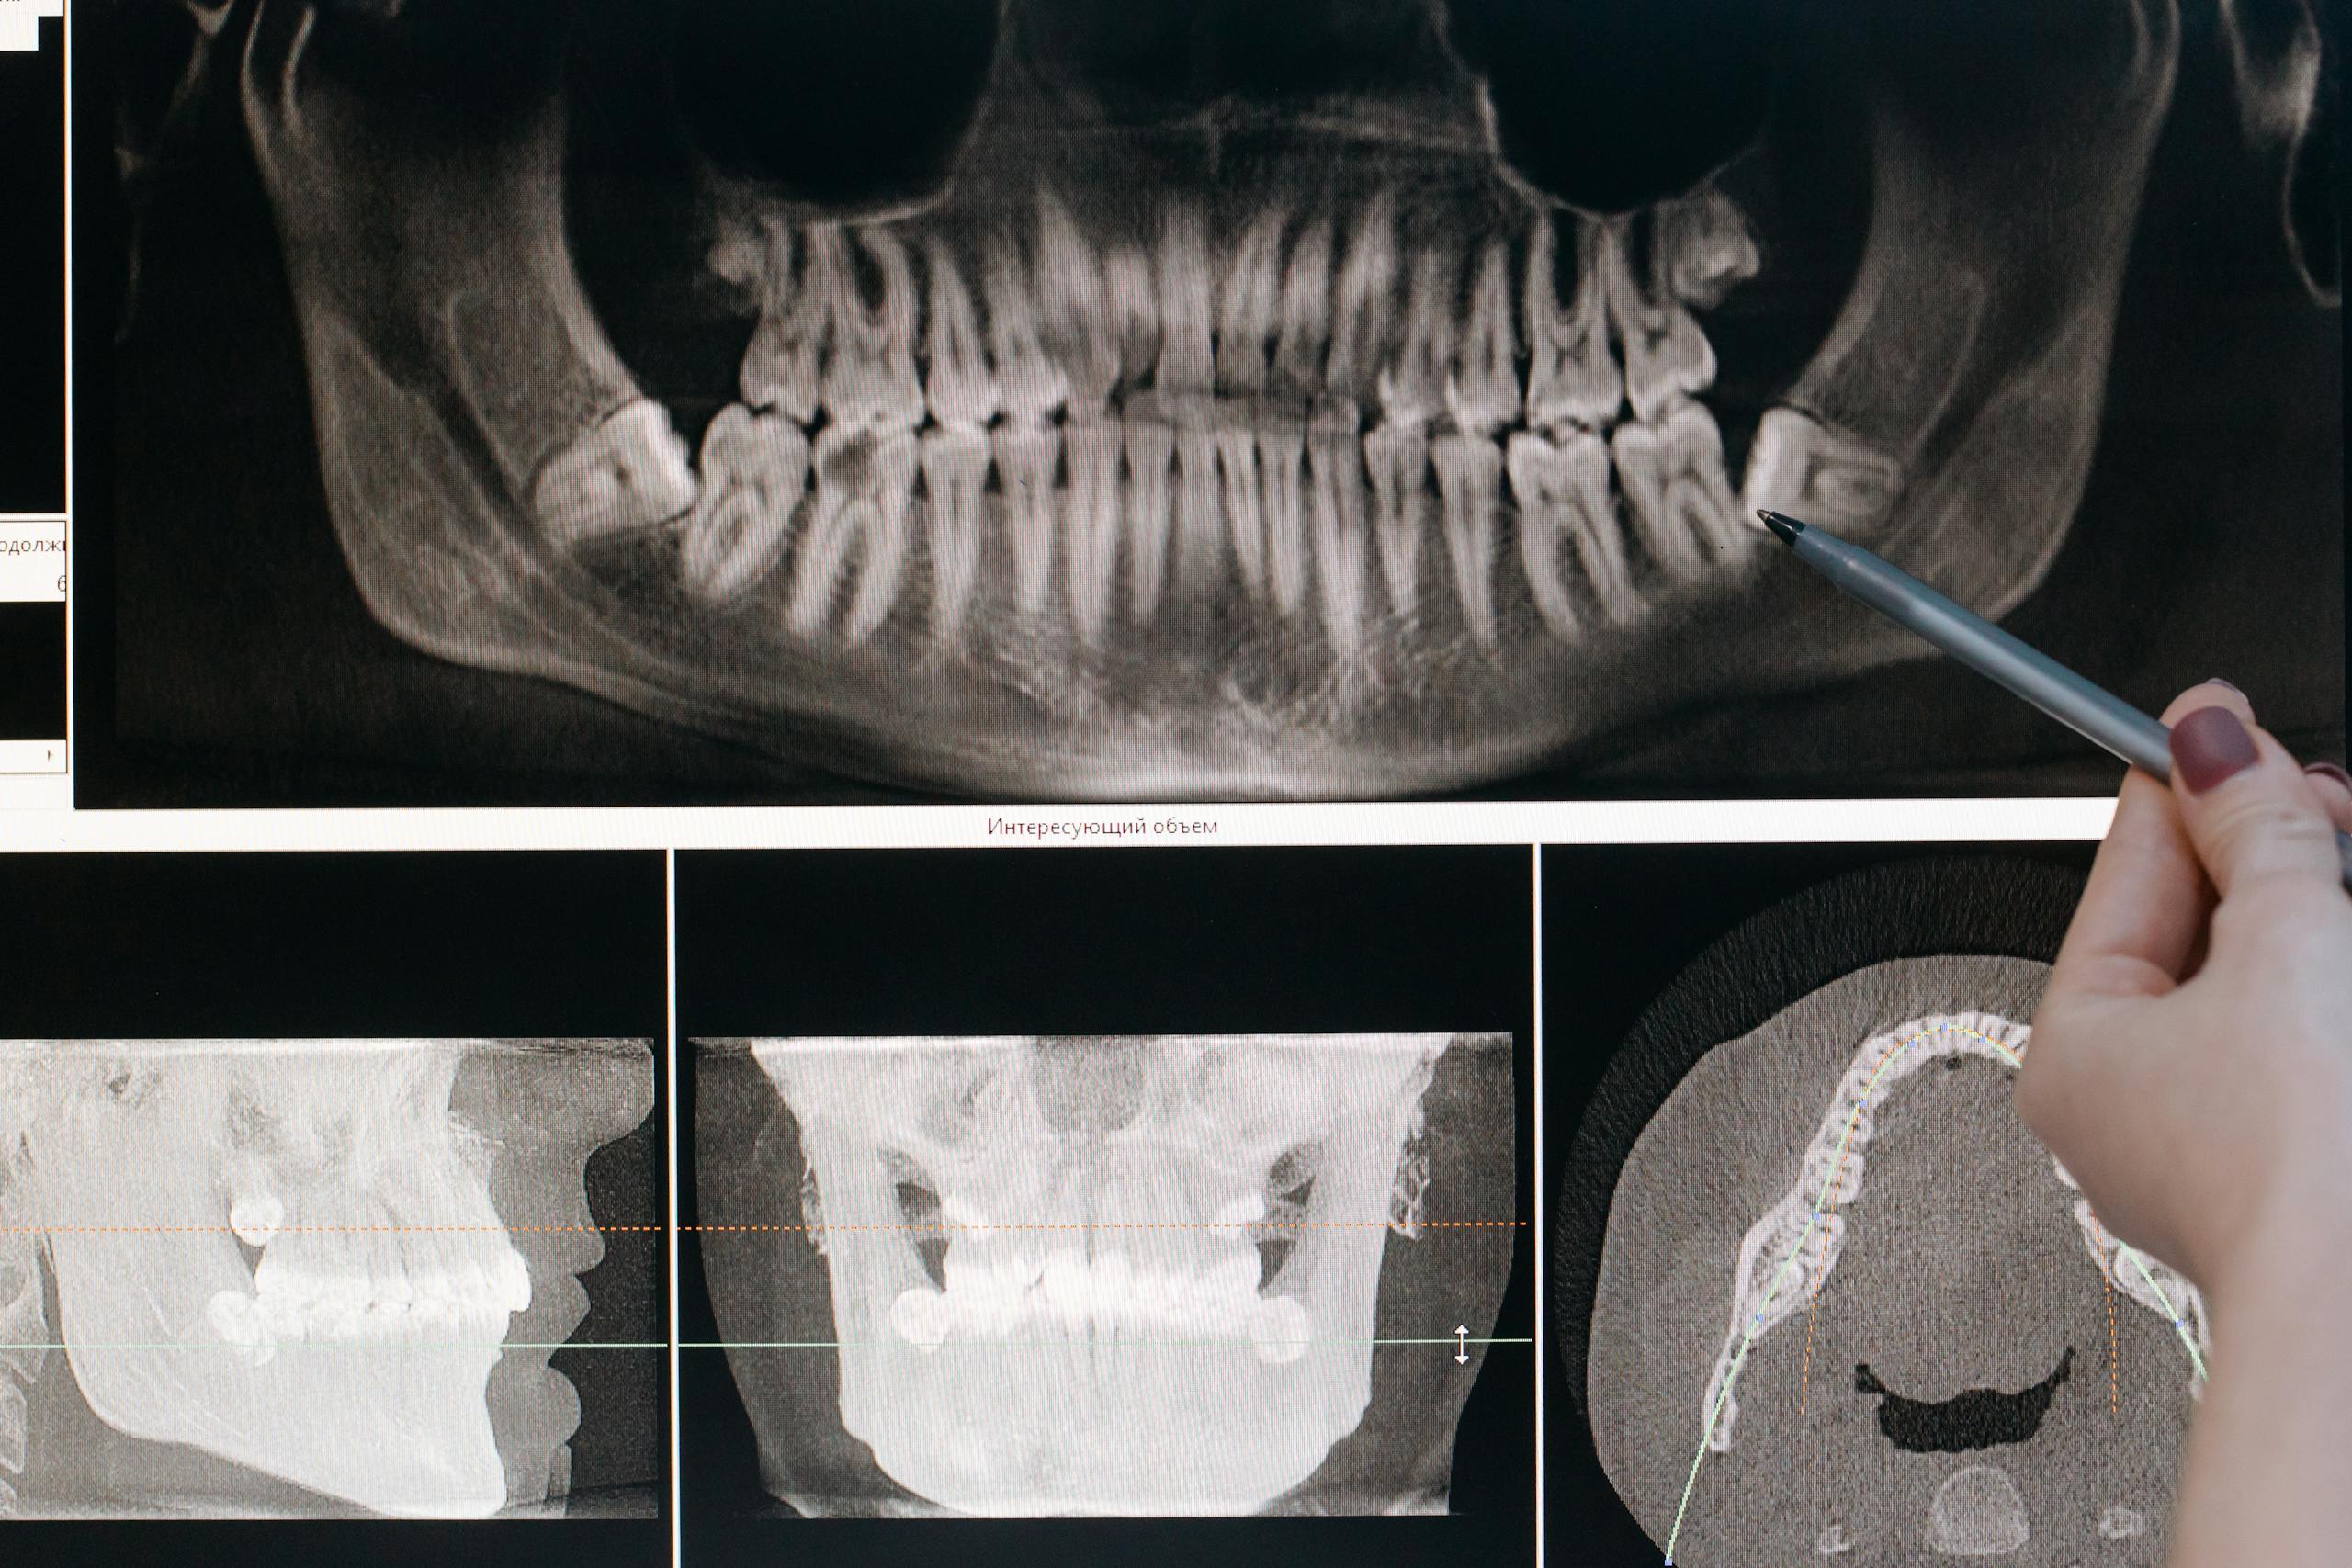

Una limpieza dental profesional elimina placa, sarro y bacterias que el cepillo no puede remover. Además, permite detectar problemas antes de que se vuelvan costosos o dolorosos.

- Revisión general de dientes y encías